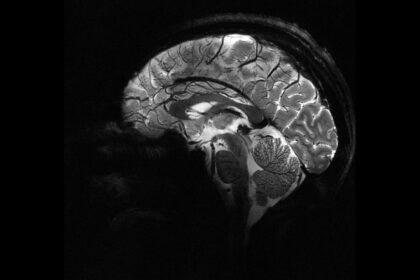

Nottingham Üniversitesi’nden bilim insanları, UK Biobank’ta yer alan 15 binden fazla yetişkinin verileriyle sağlıklı beyin yaşlanmasını tanıyan bir yapay zekâ modeli geliştirdi. Model, pandemide...